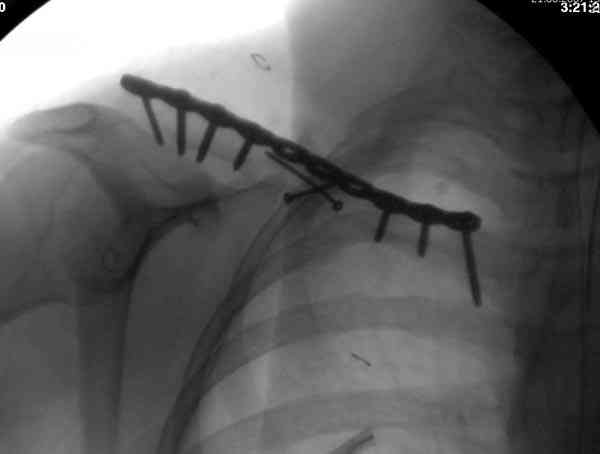

Недавно разбирали случай ложного сустава.

45 летная женщина после автоаварии, алкоголь 163 и 20 летним стажем курения.

Консервативное лечение, через 8 мес. операция Rockwood pin с костной пластикой в нашем городе другим врачом. После 8 недели падение, гвоздь удален оперирующим хирургом, больная направлена к нам. Фиксация реконструктивной пластиной с трикортикальным графтом, добавлен BMP-2. Для стабилизации фиксацию провели через акромион.

Вот уже два месяца больная также продолжает жаловаться на боли, буквально на днях удалили акромиальную часть пластины с специальной пилой с алмазным покрытием для медицинского металла. До сих пор судьба ложного сустава неизвестна....